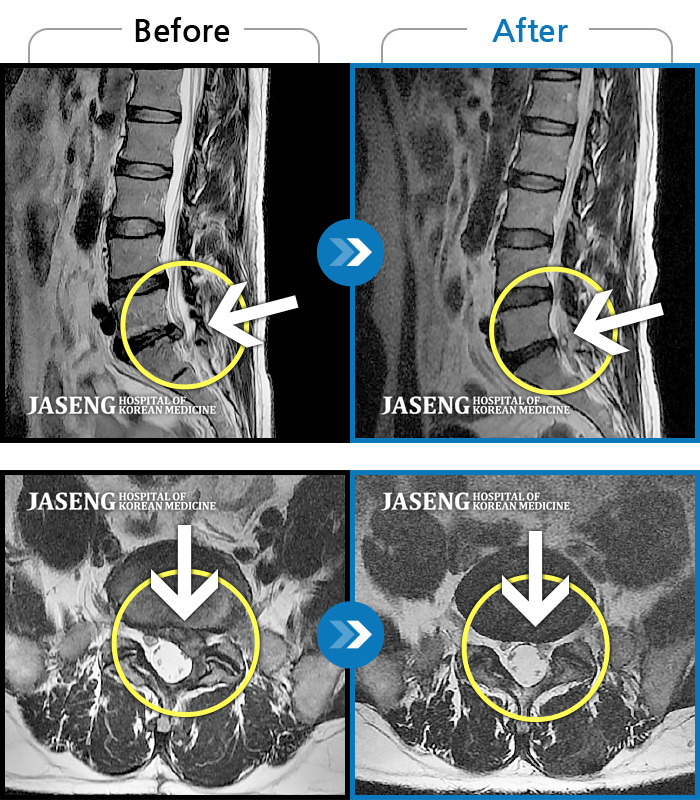

허리디스크

일산 · 배영현 원장

처음 내원 시 허리와 좌측 골반이 많이 아프고, 좌측 다리로 저림과 감각 저하가 있어서 보행이 원활하지 못했으며, 야간통으로 잠도 못 자고 통증 심하여 정상적인 활동이 힘든 상태셨습니다.

촬영시기

2023.09.16 ~ 2024.09.24

2024.10.04